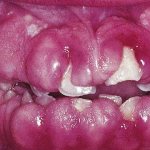

Добросовестные имплантологи в этом случае берутся за переустановку протеза. Но часто бывает и так, что пациент вынужден обращаться для переустановки имплантов в другую клинику. Это происходит по причине того, что в установке нового имплант по гарантии ему отказали или он утратил доверие к тому доктору, который проводил ему первичную операцию. Симптомами того, что имплант нуждается в замене, служат его подвижность и воспаление тканей вокруг конструкции. В этой ситуации появится болезненность, кровоточивость, может выделяться гной.

Такое состояние называется периимплантитом. В дальнейшем происходит отторжение импланта. Если врач определяет, что срок службы конструкции подошел к концу, назначается хирургическая операция по извлечению стержня из челюсти. Повторно ставить имплант можно через 1−2 месяца. Если к его установке выявлены противопоказания, пациенту предлагают альтернативные методы протезирования.